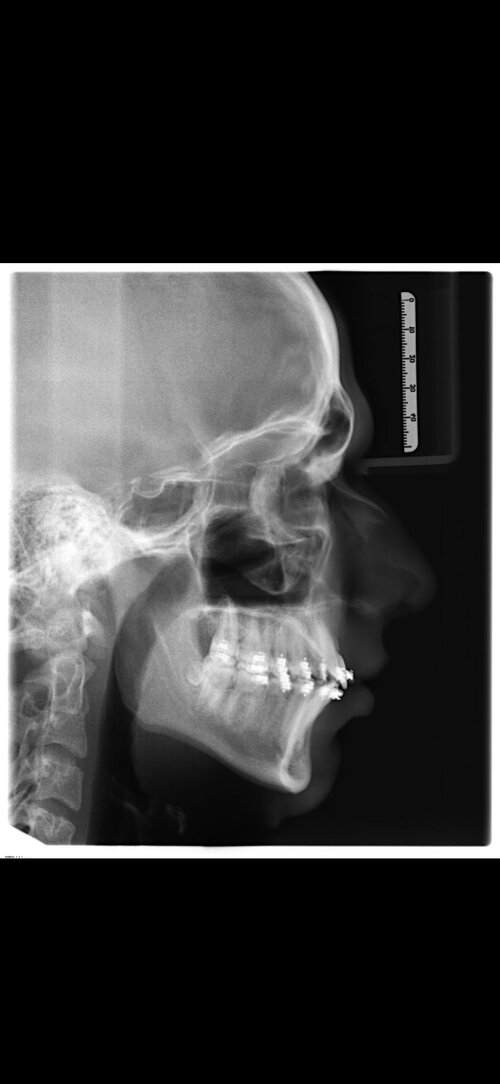

I'm getting bimax and genio in 10 days performed by Dr Dr Kater (Frankfurt am Main, Germany). It'll be payed privat but i don't know what i can expect... here are some pics, i'll upload the results as soon as the bloat is gone.